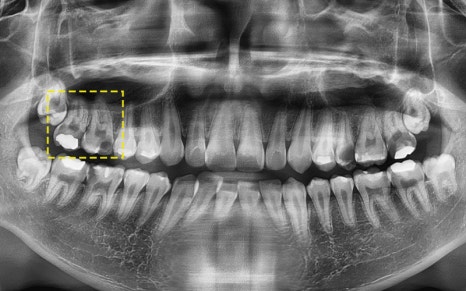

Now, let us introduce the story of a 19-year-old patient

who chose the best implant instead.

🔷 A story about a patient who chose the best implant

2025.05.25

This patient is only 19 years old.

At a young age, they lost a molar due to tooth decay,

and decided to undergo implant treatment.

However, this patient required special consideration.

“They’re still too young.

They’ll need to use this implant for decades to come.”

2025.05.31

So we recommended and performed surgery using

Swiss Straumann implants, which are recognized

as the longest-lasting and strongest in the world!